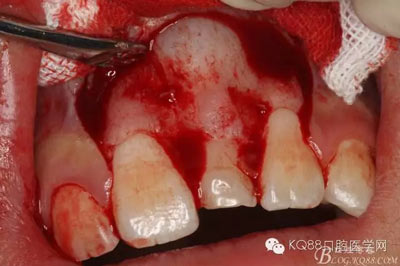

圖9.超聲骨刀去除隆起的骨壁

圖10. 形成梯形骨縫

圖11.掀開骨壁。摘除牙瘤及牙囊組織

圖12.摘除囊壁后,暴露出21的切端